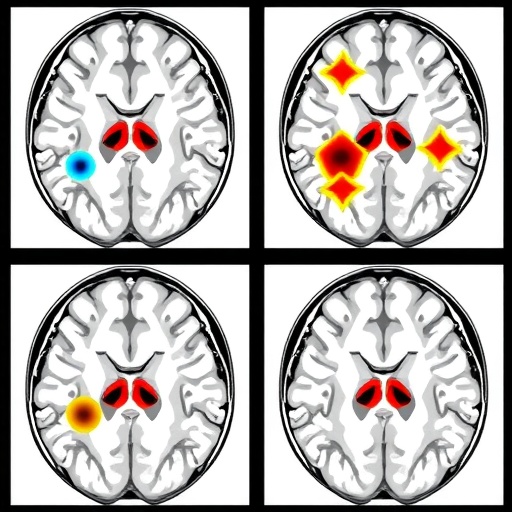

In a groundbreaking study set to transform the landscape of medical imaging, researchers have developed a robust deep learning ensemble framework aimed at the accurate classification of brain tumors. This innovative approach combines multiple machine learning techniques to improve diagnostic performance significantly, a critical advancement given the vital role of precision in brain tumor treatment and management. The work, led by Kukadiya, H., Arora, N., and Meva D., demonstrates how advanced artificial intelligence can lead to faster and more reliable diagnoses in a field where time and accuracy are paramount.

The methodology of the study is particularly noteworthy. By employing a combination of convolutional neural networks (CNNs) and decision trees, the researchers effectively tapped into the strengths of each model. CNNs, renowned for their image processing capabilities, were responsible for extracting intricate features from the medical images, while the decision trees contributed to making logical classifications based on these extracted features. This synergy results in a powerful predictive tool that can significantly influence treatment decisions and outcomes.

Moreover, the performance metrics reported in the study are striking. The researchers achieved an unprecedented accuracy rate in brain tumor classification, significantly higher than previous benchmarks. This leap in performance can be attributed to the ensemble nature of the model, which mitigates the limitations inherent in individual learning algorithms. By aggregating the strengths and compensating for the weaknesses of different models, the ensemble framework showcases an evolutionary step forward in medical imaging diagnostics.